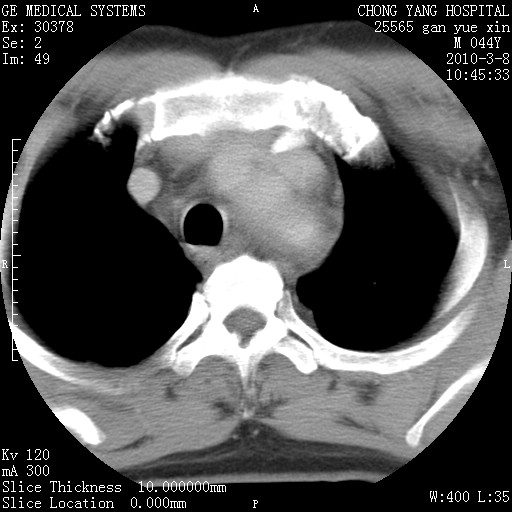

标题: CT24940:主动脉增强,典型病例。 [打印本页]

标题: CT24940:主动脉增强,典型病例。

夹层动脉瘤。

动脉夹层

夹层动脉瘤,典型

主动脉夹层。

动脉夹层的分型:

⒈debakey分型:根据主动脉夹层累及部位,分为三型:ⅰ型:原发破口位于升主动脉或主动脉弓部,夹层累及升主动脉、主动脉弓部、胸主动脉、腹主动脉大部或全部,少数可累及髂动脉。ⅱ型:原发破口位于升主动脉,夹层累及升主动脉,少数可累及部分主动脉弓。ⅲ型:原发破口位于左锁骨下动脉开口远端,根据夹层累及范围又分为ⅲa,ⅲb。ⅲa型:夹层累及胸主动脉。ⅲb型:夹层累及升主动脉、腹主动脉大部或全部。少数可累及髂动脉。

⒉stanford分型:a型:夹层累及升主动脉,无论远端范围如何。b型:夹层累及左锁骨下动脉开口以远的降主动脉。

夹层动脉瘤,少量胸水

夹层动脉瘤;左侧少量胸腔积液。